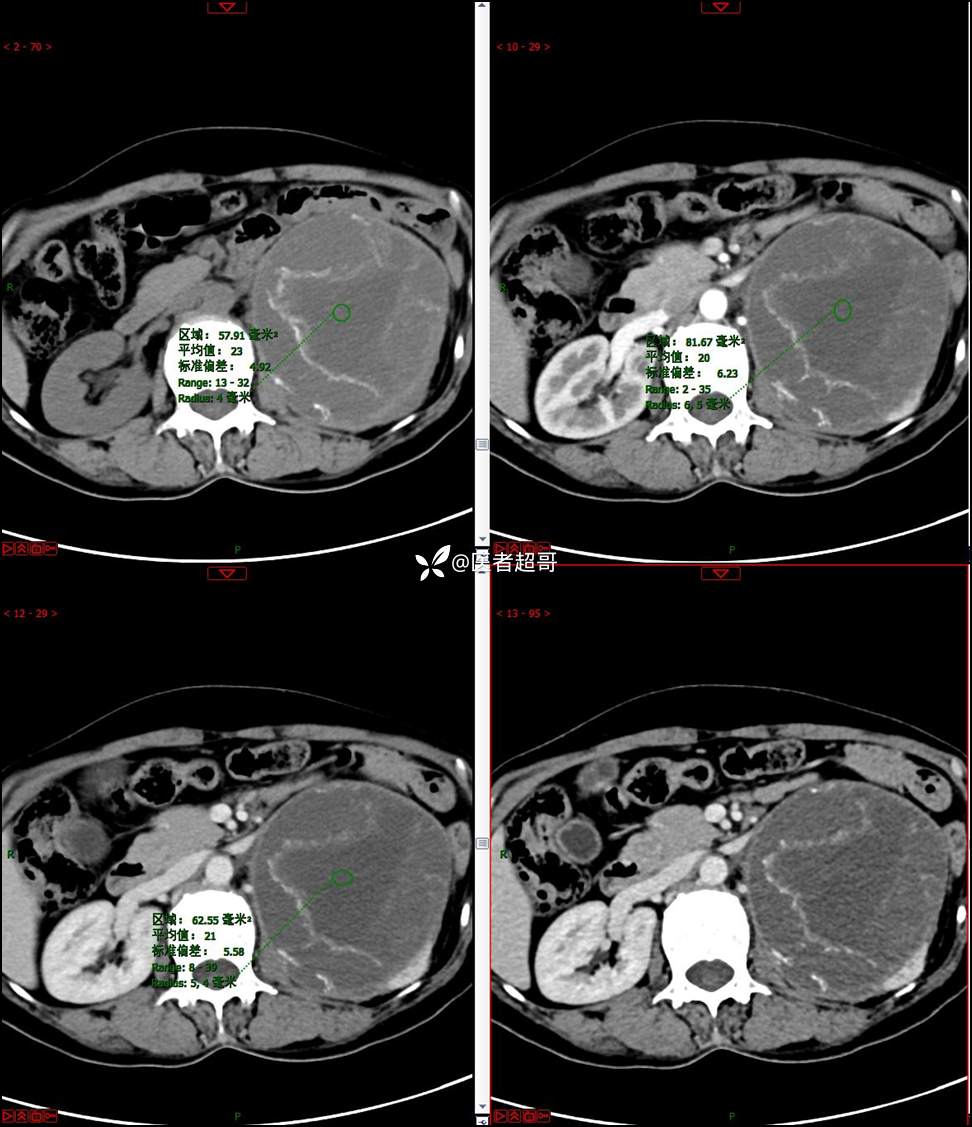

【影诊笔记768】肾脏肿瘤?肾上腺肿瘤?请诊断分析!

女 57岁 0200908 01

主 诉:发现左肾肿物7月余

现病史:患者7月前因左侧腹部疼痛不适,就诊市人民医院,行CT平扫:左侧肾上腺区混杂密度肿块,考虑肿瘤合并出血,行保守治疗后症状缓解出院,左侧下腹部及左侧髋部疼痛不适,无尿频、尿急、尿痛,无肉眼血尿,无寒战、发热,今患者为求进一步诊治,就诊我院,门诊以“左肾肿物”为诊断收入院,患者自发病以来,神志清,精神可,饮食睡眠可,小便如上述,大便正常,体重未见明显改变。